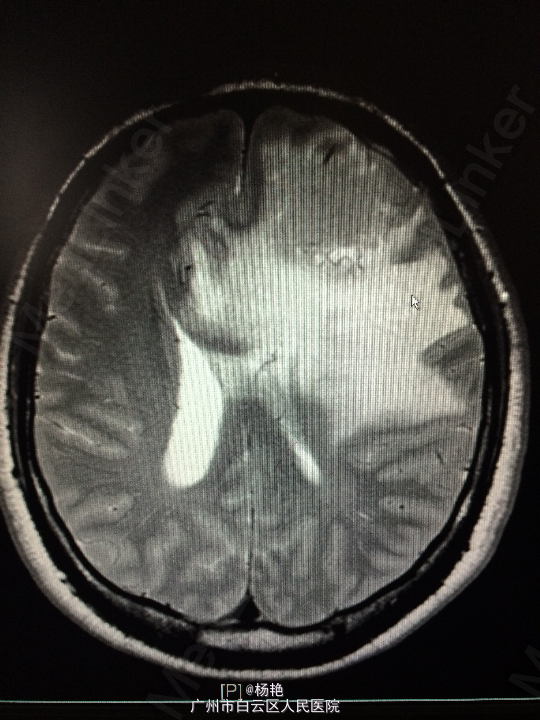

主诉:反复头痛2年加重1周 病史:患者诉两年前无明显诱因反复出现头晕头痛不适,近一周来症状加重,无恶心呕吐、无行走不稳、肢体乏力、意识障碍等。遂至当地医院诊治,行头颅CT、MR检查均提示颅内占位,良性可能性大,考虑脑膜瘤。今患者为求进一步治疗而入我院。

查体:神经系统查体未见明显异常 辅助检查:头颅MR提示:左侧额叶区域较大类圆形肿物,多考虑脑膜瘤可能;大脑前动脉及中动脉受压,中线偏移。

诊断:左额叶脑膜瘤 处理:在静脉全麻下行左侧额底脑膜瘤切除术,术后病理提示:脑膜瘤

术后患者左侧视力稍模糊,无其他不适,出院 讨论:脑膜瘤属于良性肿瘤,生长慢,病程长。因肿瘤呈膨胀性生长,病人往往以头疼和癫痫为首发症状。根据肿瘤位置不同,还可以出现视力、视野、嗅觉或听觉障碍及肢体运动障碍等。在老年人,尤以癫痫发作为首发症状多见。颅压增高症状多不明显,尤其在高龄病人。在CT检查日益普及的情况下,许多患者仅有轻微头痛,甚至经CT扫描偶然发现为脑膜瘤。因肿瘤生长缓慢,所以肿瘤往往长的很大,而临床症状还不严重。临近颅骨的脑膜瘤常可造成骨质的变化。手术切除脑膜瘤是最有效的治疗手段。随着显微手术技术的发展,脑膜瘤的手术效果不断提高,使大多数病人得以治愈。